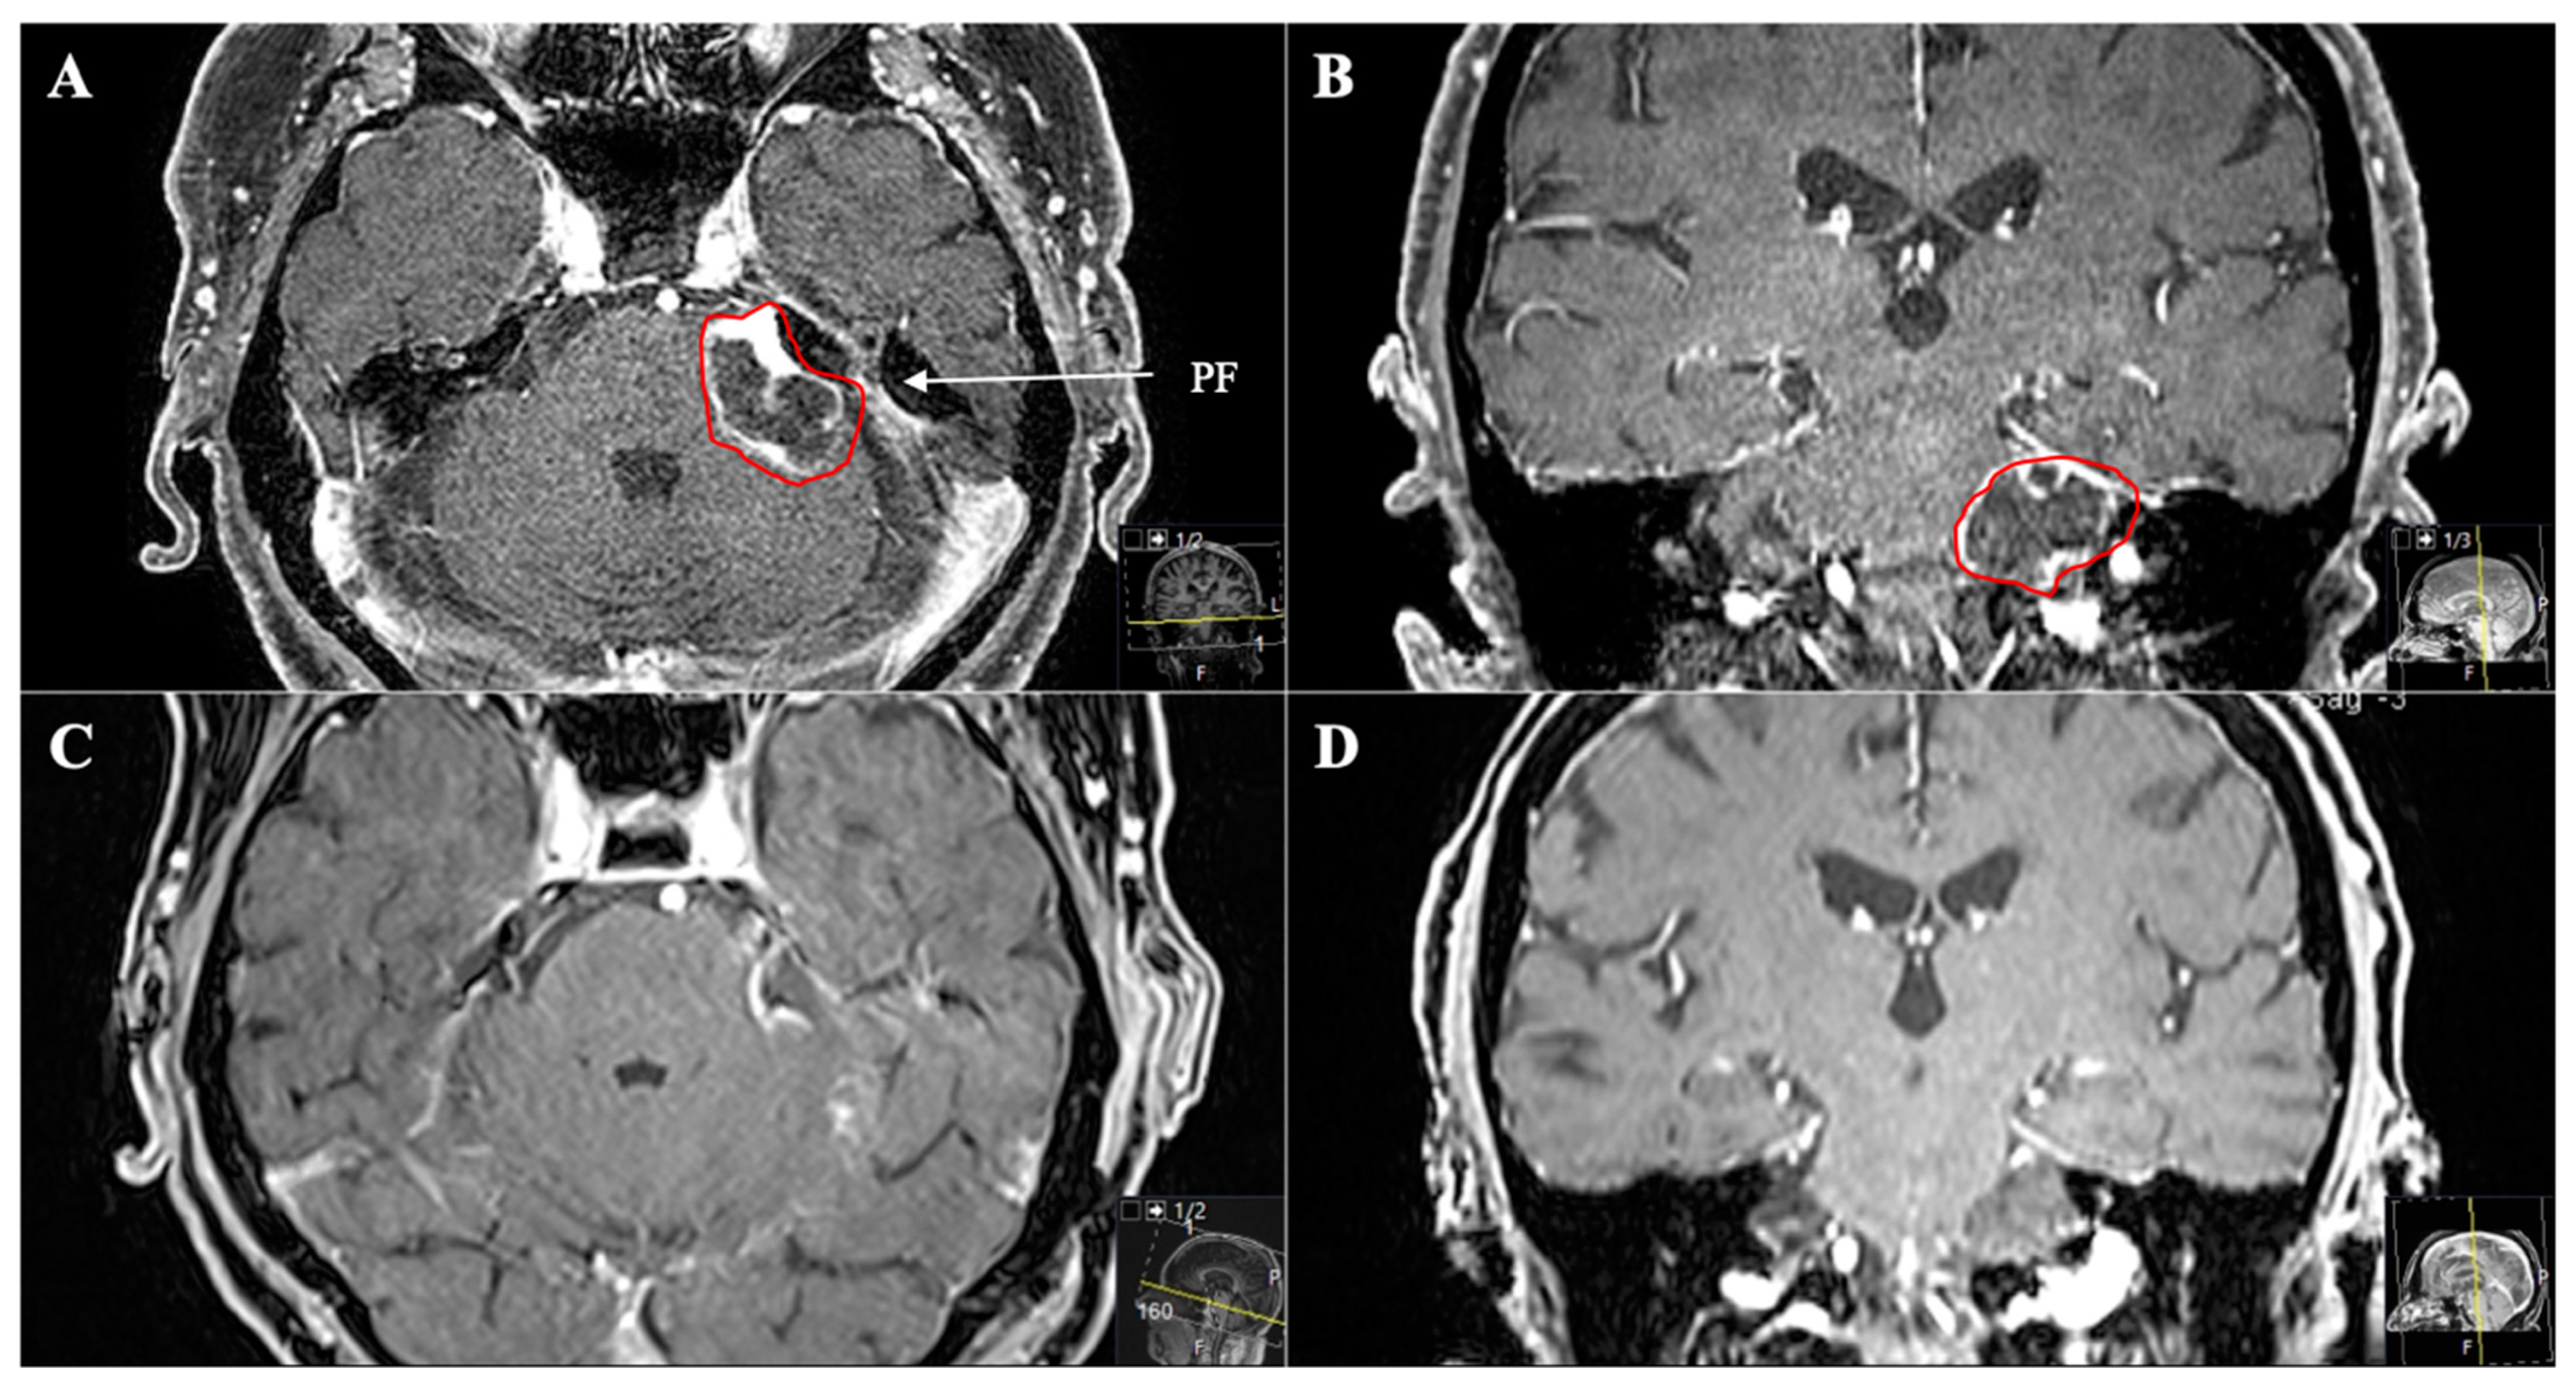

Figure 7. A 45-year-old female patient presented with left-sided visual impairment and headache. (A) Preoperative axial T1-weighted gadolinium-enhanced MRI and (B) axial CT, showing an optic-canal-compressing trigeminal schwannoma with a cystic part in Meckel’s cave in the middle fossa (MF, Samii Type A). Note how the foramen rotundum is widened (red circle). (C) Postoperative axial and (D) coronal MRI control, indicating complete resection via a transnasal endoscopic (transpterygoid) approach using a nasoseptal flap.